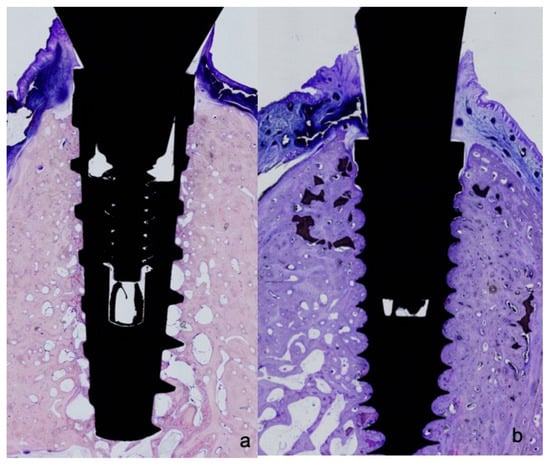

All biopsies were processed using the same protocol, performing ground sectioning according to the method that was described by Donath & Breuner (1982) [27], designed to evaluate peri-implant soft tissue healing and bone remodeling. Samples were dehydrated in increasing grades of ethanol up to 100% and were embedded in a glycol methacrylate resin (Technovit 7200 VLC, Kulzer, Wehrheim, Germany). Then, the samples were polymerized and sectioned at the buccal-lingual plane using a diamond saw (Exakt, Apparatebau, Norderstedt, Germany). Sections were cut from each biopsy unit, from the center of the implant using a high-precision diamond disk to about 100 μm thickness and ground to approximately 40 μm final thickness with an Exakt 400s CS grinding device (Exakt, Apparatebau, Norderstedt, Germany). Each section was stained using toluidine blue stain (Figure 2 and Figure 3).

Figure 2. (a) Histological preparations representing the outcome after 8 weeks healing showing polished neck and micro-ring neck design of the Blue Sky implant; and (b) outcome after eight weeks healing of micro-ring neck design of the C1 implant.

Figure 3. (a) Histological preparations representing the outcome after 8 weeks healing showing open-thread neck design of the IPX implant; and, (b) after eight weeks healing showing (open-thread) double-spiral neck design of the Facility implant.